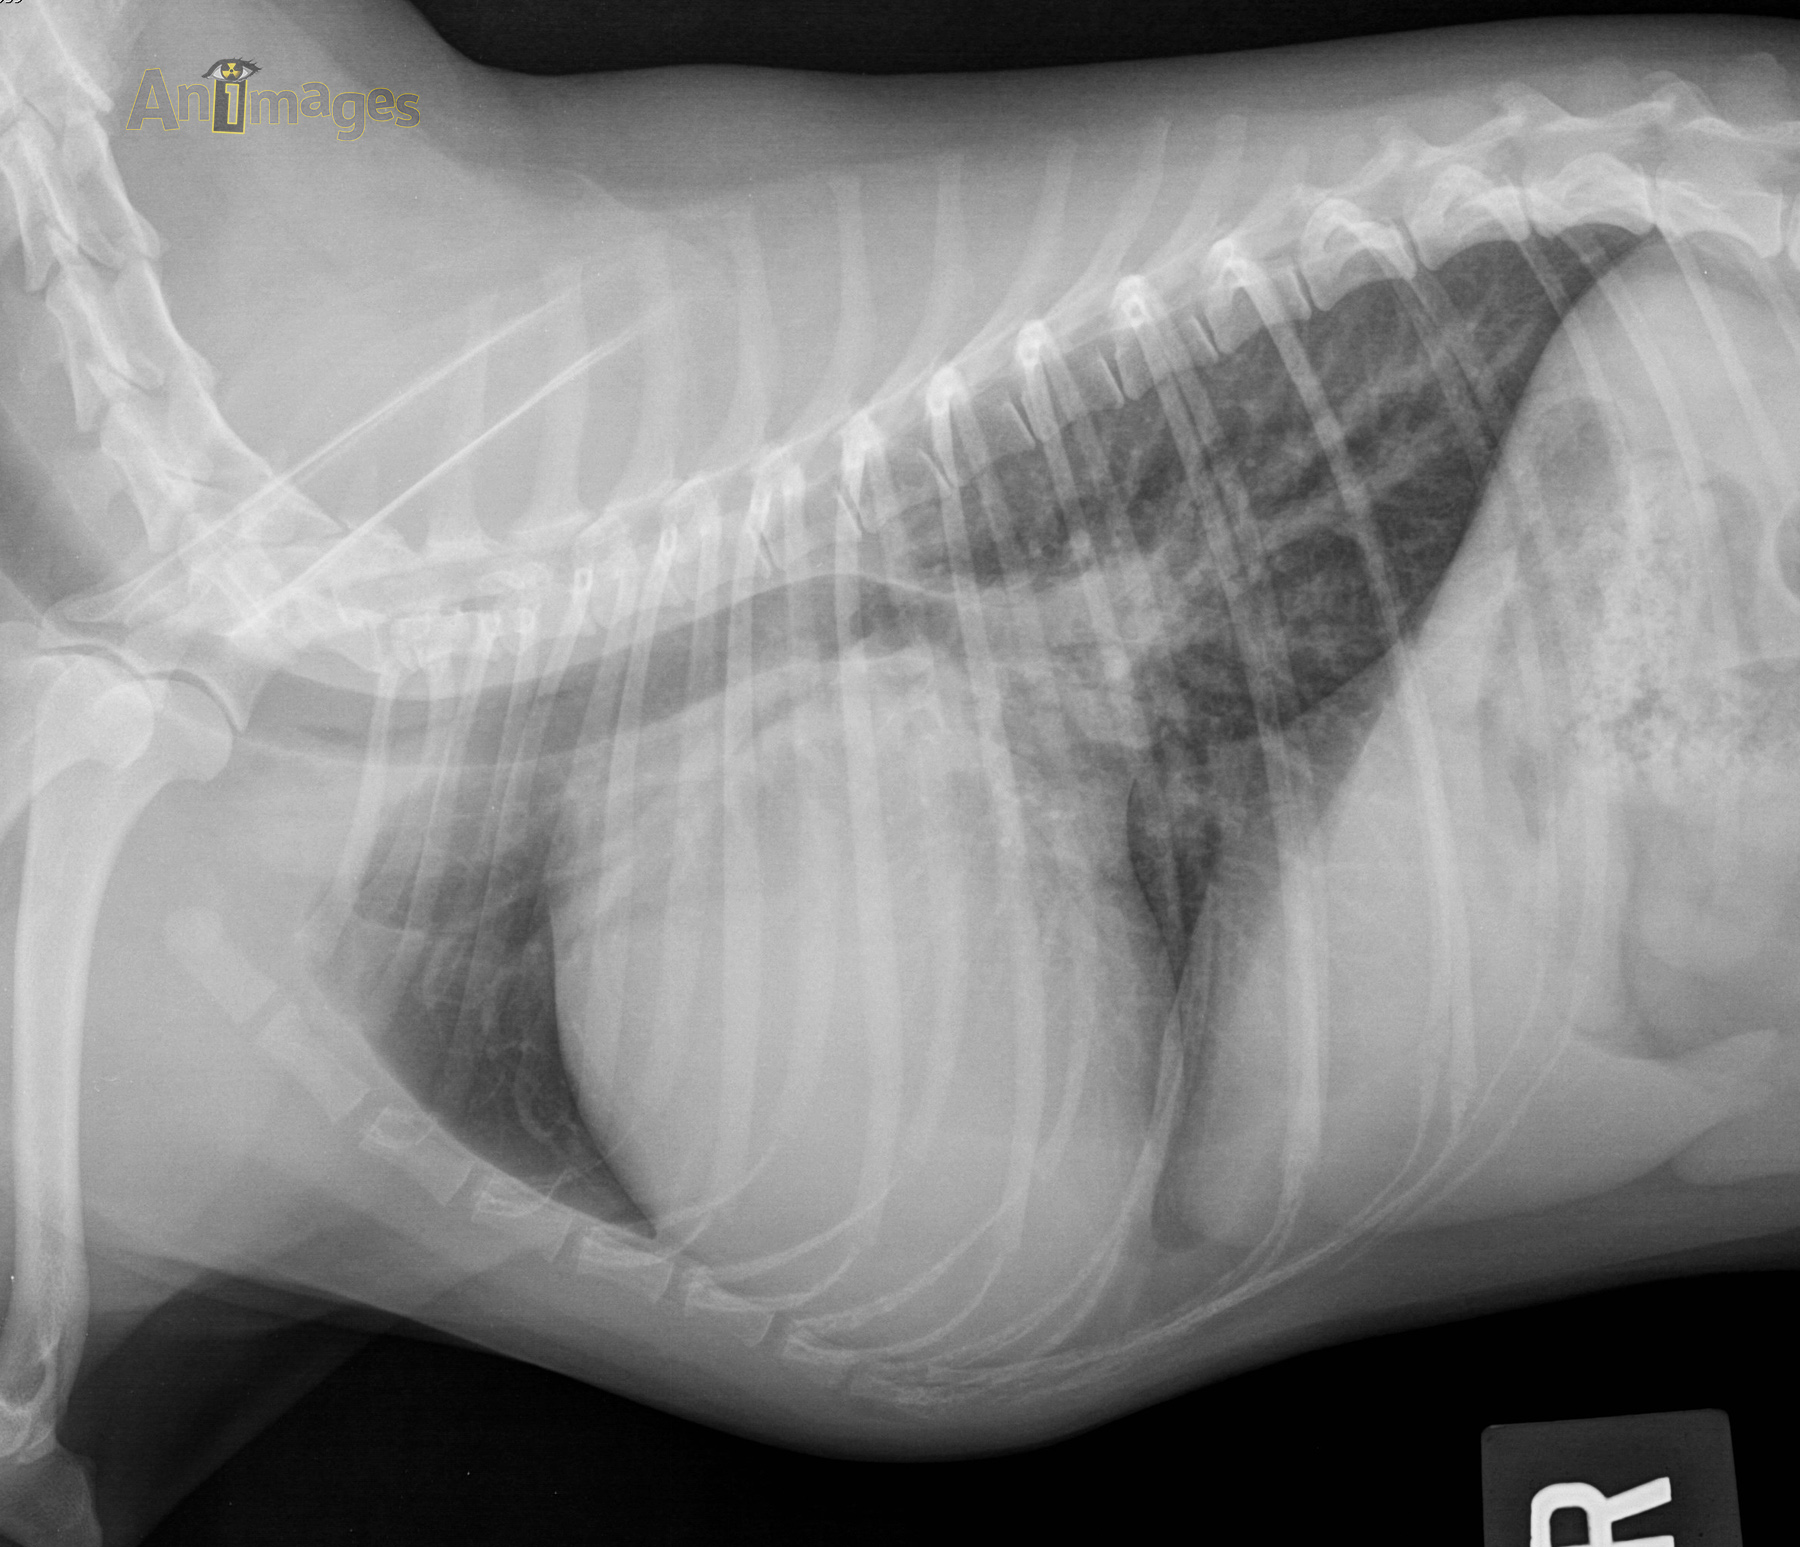

lat D_1

Latérale droite